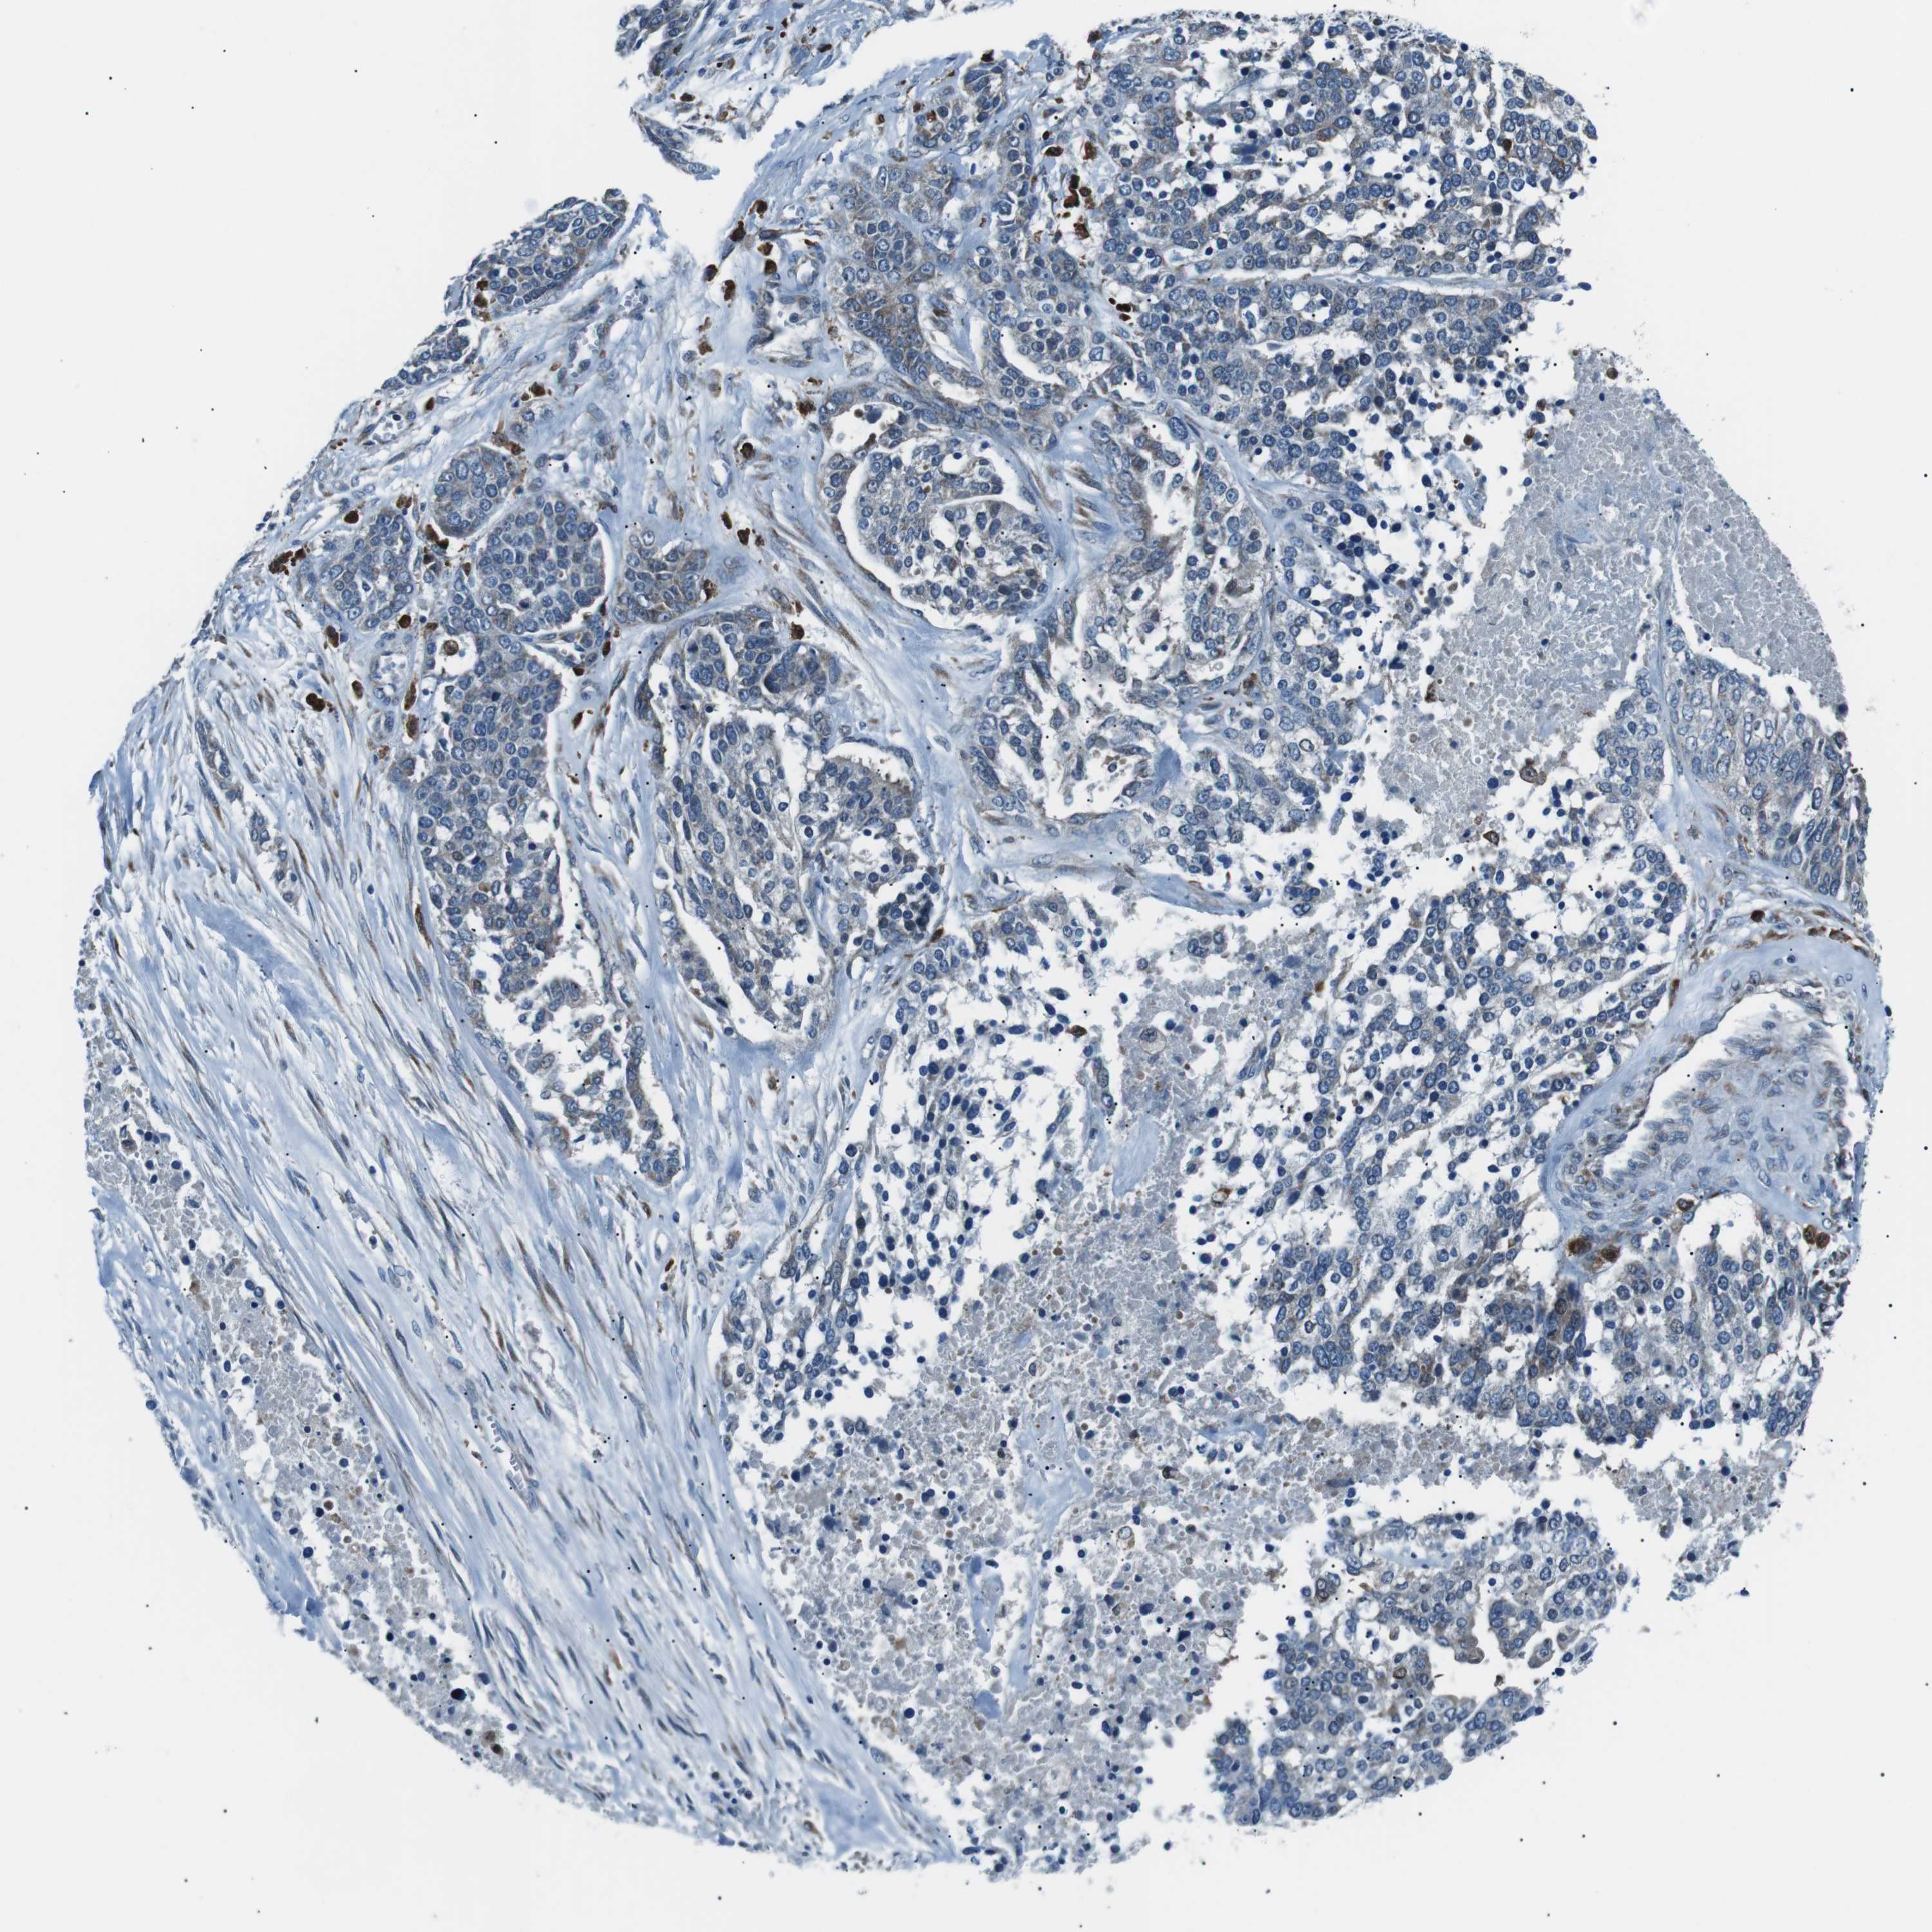

OVARIAN CANCER - Protein expressioni

A mouse-over function shows sample information and annotation data. Click on an image to view it in a full screen mode. Samples can be filtered based on level of antibody staining by selecting one or several of the following categories: high, medium, low and not detected. The assay and annotation is described here.

Note that samples used for immunohistochemistry by the Human Protein Atlas do not correspond to samples in the TCGA dataset.

Antibody stainingi

Antibody staining in the annotated cell types in the current human tissue is reported as not detected, low, medium, or high, based on conventional immunohistochemistry profiling in selected tissues. This score is based on the combination of the staining intensity and fraction of stained cells.

Each image is clickable and will lead to virtual microscopy that enables deeper exploration of all samples and also displays staining intensity scores, fraction scores and subcellular localization as well as patient and tissue information for each sample.

Antibody HPA038309

Antibody HPA038310

Antibody CAB009333

Antibody CAB016291

Cystadenocarcinoma, serous, NOS

Carcinoma, NOS

Cystadenocarcinoma, mucinous, NOS

Carcinoma, endometroid